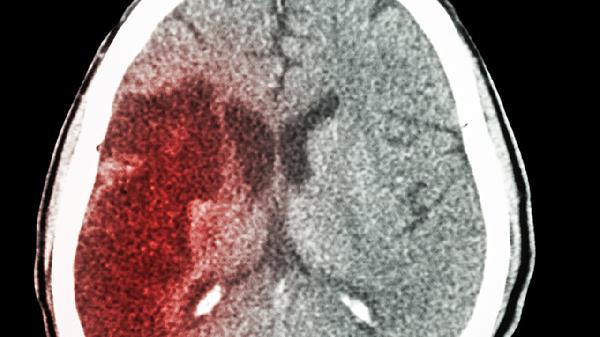

脑血管经历堵塞后变得格外敏感,温度骤变会导致血管异常收缩。头部分布着大量浅表血管,戴上帽子就像给血管装上恒温器,避免寒冷刺激引发的二次伤害。